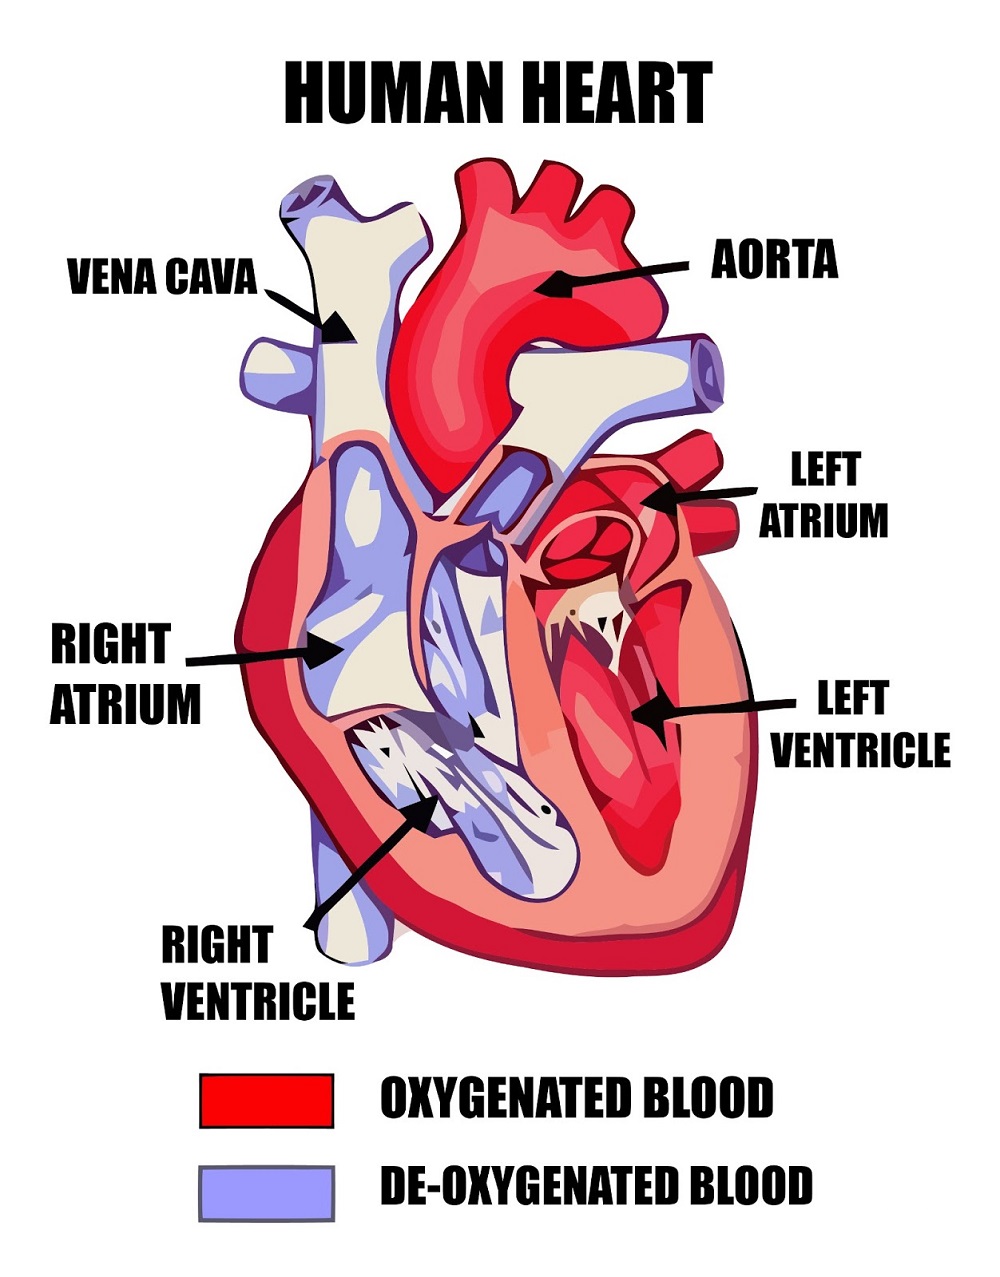

What are the parts that make up a human heart? Diagrams and More | Human heart diagram, Heart

What are the parts that make up a human heart? Diagrams and More | Human heart diagram, Heart  Human heart by kortney16 on DeviantArt

Human Heart Diagram Without Labels - koibana.info | Human heart diagram, Heart diagram, Human  Human Heart Diagrams | 101 Diagrams

Human Heart Diagrams | 101 Diagrams  Human Heart Simple Drawing at GetDrawings | Free download

Anatomy of the Heart: Physiology | Health Life Media  Human Heart Anatomy Drawing at GetDrawings | Free download

Human Heart - Circulatory System | OER Commons  de Location Of Human Heart In Body mar webmds heart anatomy page provides a detailed image of

Scientific medical illustration of parts of the human heart 685453 Vector Art at Vecteezy  Human Heart Drawing Outline at GetDrawings | Free download

Anatomy of the human heart  Human Heart Drawing Line Work stock vector art 481404348 | iStock